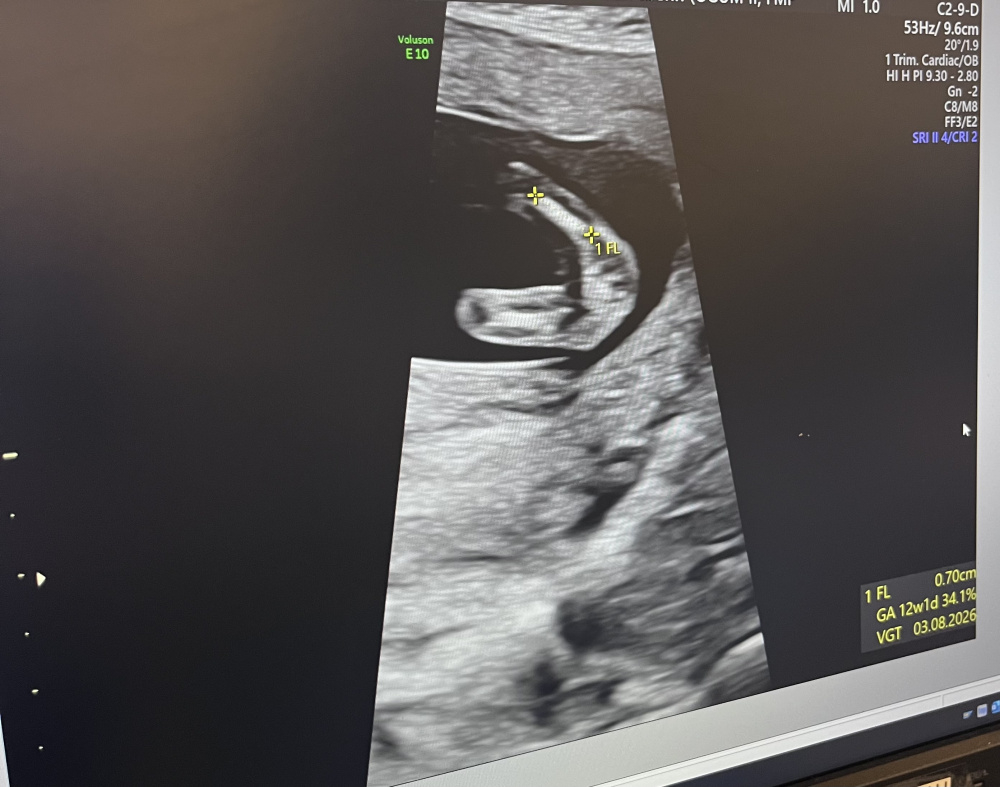

Würd aufgrund der 3 Stricherl auch auf ein Mäderl tippen.